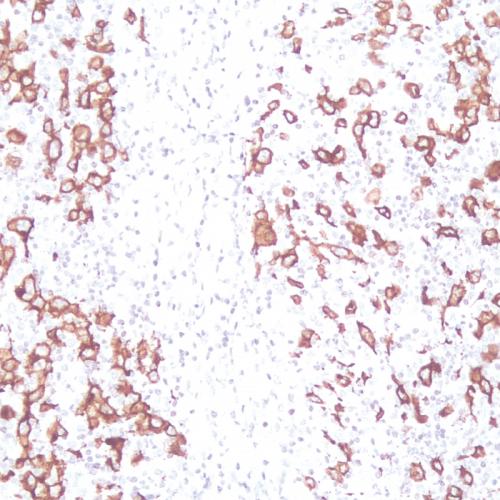

• CD31

CD31

CD31抗體試劑(免疫組織化學(xué)) 閩廈械備20180069號(hào)